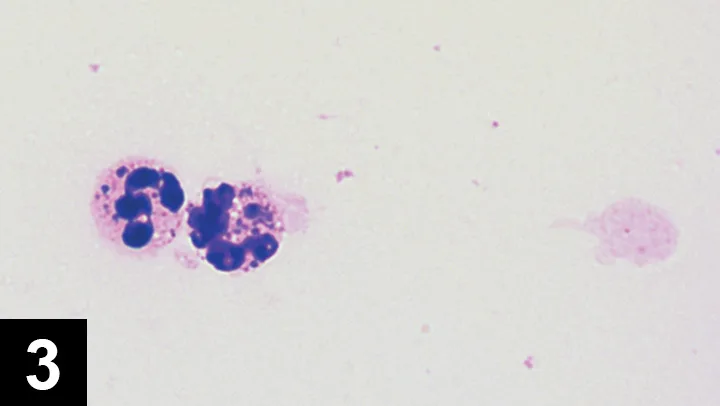

Inflammatory arthropathy may be caused by infection or immune-mediated disease. Most infections are caused by bacteria; cell counts in these cases generally exceed 15,000 cells/µL (see Acquiring Cell Counts) and are predominantly neutrophilic. Gram staining and microscopic evaluation can be used to identify bacteria, but bacteria are only seen in 25% of septic arthritis cases. When such a cytologic profile has been identified, a sample should be submitted for aerobic and anaerobic bacterial culture (see If Suppurative Inflammation Is Seen). Even when bacterial infection is present, false-negative culture findings are common. Results are false-negative in about 30% to 50% of dogs with septic arthritis.1 Therefore, if septic arthritis is suspected, the clinician should institute an empirical antibiotic trial. Synovial tissue samples can also be collected for bacterial culture to improve sensitivity. Cephalexin, amoxicillin–clavulanate, or clindamycin are first-line antibiotics against Staphylococcus and Streptococcus spp, common causes of joint infection in small animals. If only one joint has suppurative inflammation, bacterial infection is probable.

Radiography to evaluate for erosive joint disease (rheumatoid arthropathy*)

Figure 4 Lateral view of carpus with erosive lesions of the joint, which is seen with rheumatoid arthritis.

If suppurative inflammation is evident in multiple joints, immune-mediated arthritis (eg, idiopathic immune-mediated polyarthritis, rheumatoid arthritis, systemic lupus erythematosus) is a leading cause. Finally, tick-borne diseases (eg, Rocky Mountain spotted fever, ehrlichiosis, Lyme disease) may also cause suppurative inflammation in single or multiple joints.